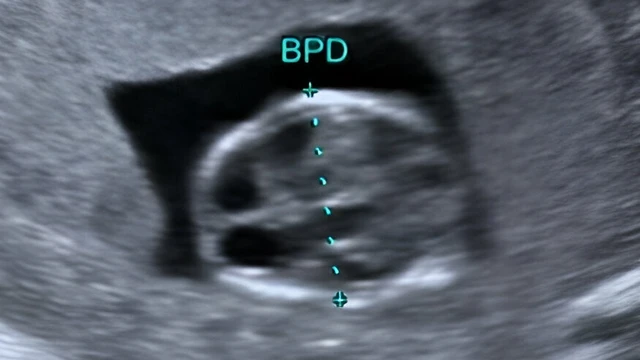

Chỉ số đường kính lưỡng đỉnh thai 36 tuần như thế nào là bình thường? Đây là chỉ số phản ánh sự phát triển kích thước hộp sọ thai nhi, liệu có liên quan trực tiếp đến sự phát triển trí tuệ của bé? Các mẹ bầu hãy cùng khám phá ngay bài viết chi tiết, cung cấp đầy đủ thông tin khoa học, giúp mẹ hiểu rõ hơn về sự phát triển của con yêu.